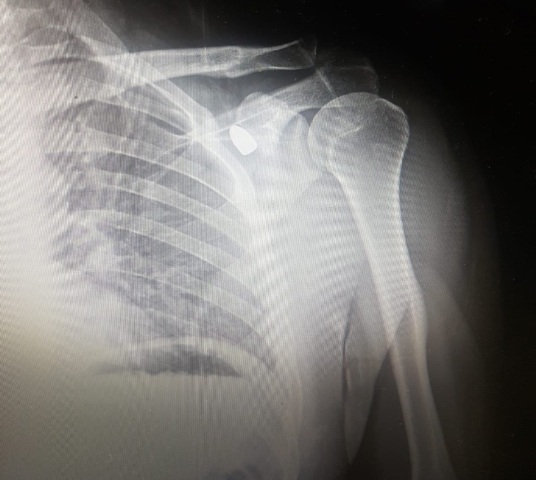

Alınan bilgiye göre, Adsız Merkez Mahallesi'ndeki çay bahçesinde arkadaşlarıyla oturan Celal Şenyiğit aniden yere yığıldı. Yaralandığı fark edilen Şenyiğit, Akşehir Devlet Hastanesine kaldırıldı. Vücuduna yorgun mermi isabet ettiği anlaşılan Şenyiğit, hastanede gazetecilere yaptığı açıklamada, çay bahçesinde otururken ses duyduğunu ve vücudunda yanma hissettiğini söyledi. Akan kanı gördüğünü belirten Şenyiğit, şunları kaydetti: "Arkadaşlarım beni hemen hastaneye kaldırdı. Hastanede röntgen çekildi ve vücuduma 9 milimetre çapında bir merminin isabet ettiği söylendi. Muhtemelen çevremizdeki düğünlerden birinde havaya sıkılan kurşunlardan gelen yorgun bir mermiymiş bu. Sol omzum ile köprücük kemiği arasında bulunan mermi, önümüzdeki günlerde Akşehir Devlet Hastanesinde gerçekleştirilecek ameliyatla alınacak. Lütfen düğünlerde daha duyarlı olalım, silah atmayalım. Bu, bir çocuğa da gelebilirdi veya benim başıma gelip ölümüme neden olabilirdi." Olayla ilgili soruşturma sürüyor.aa